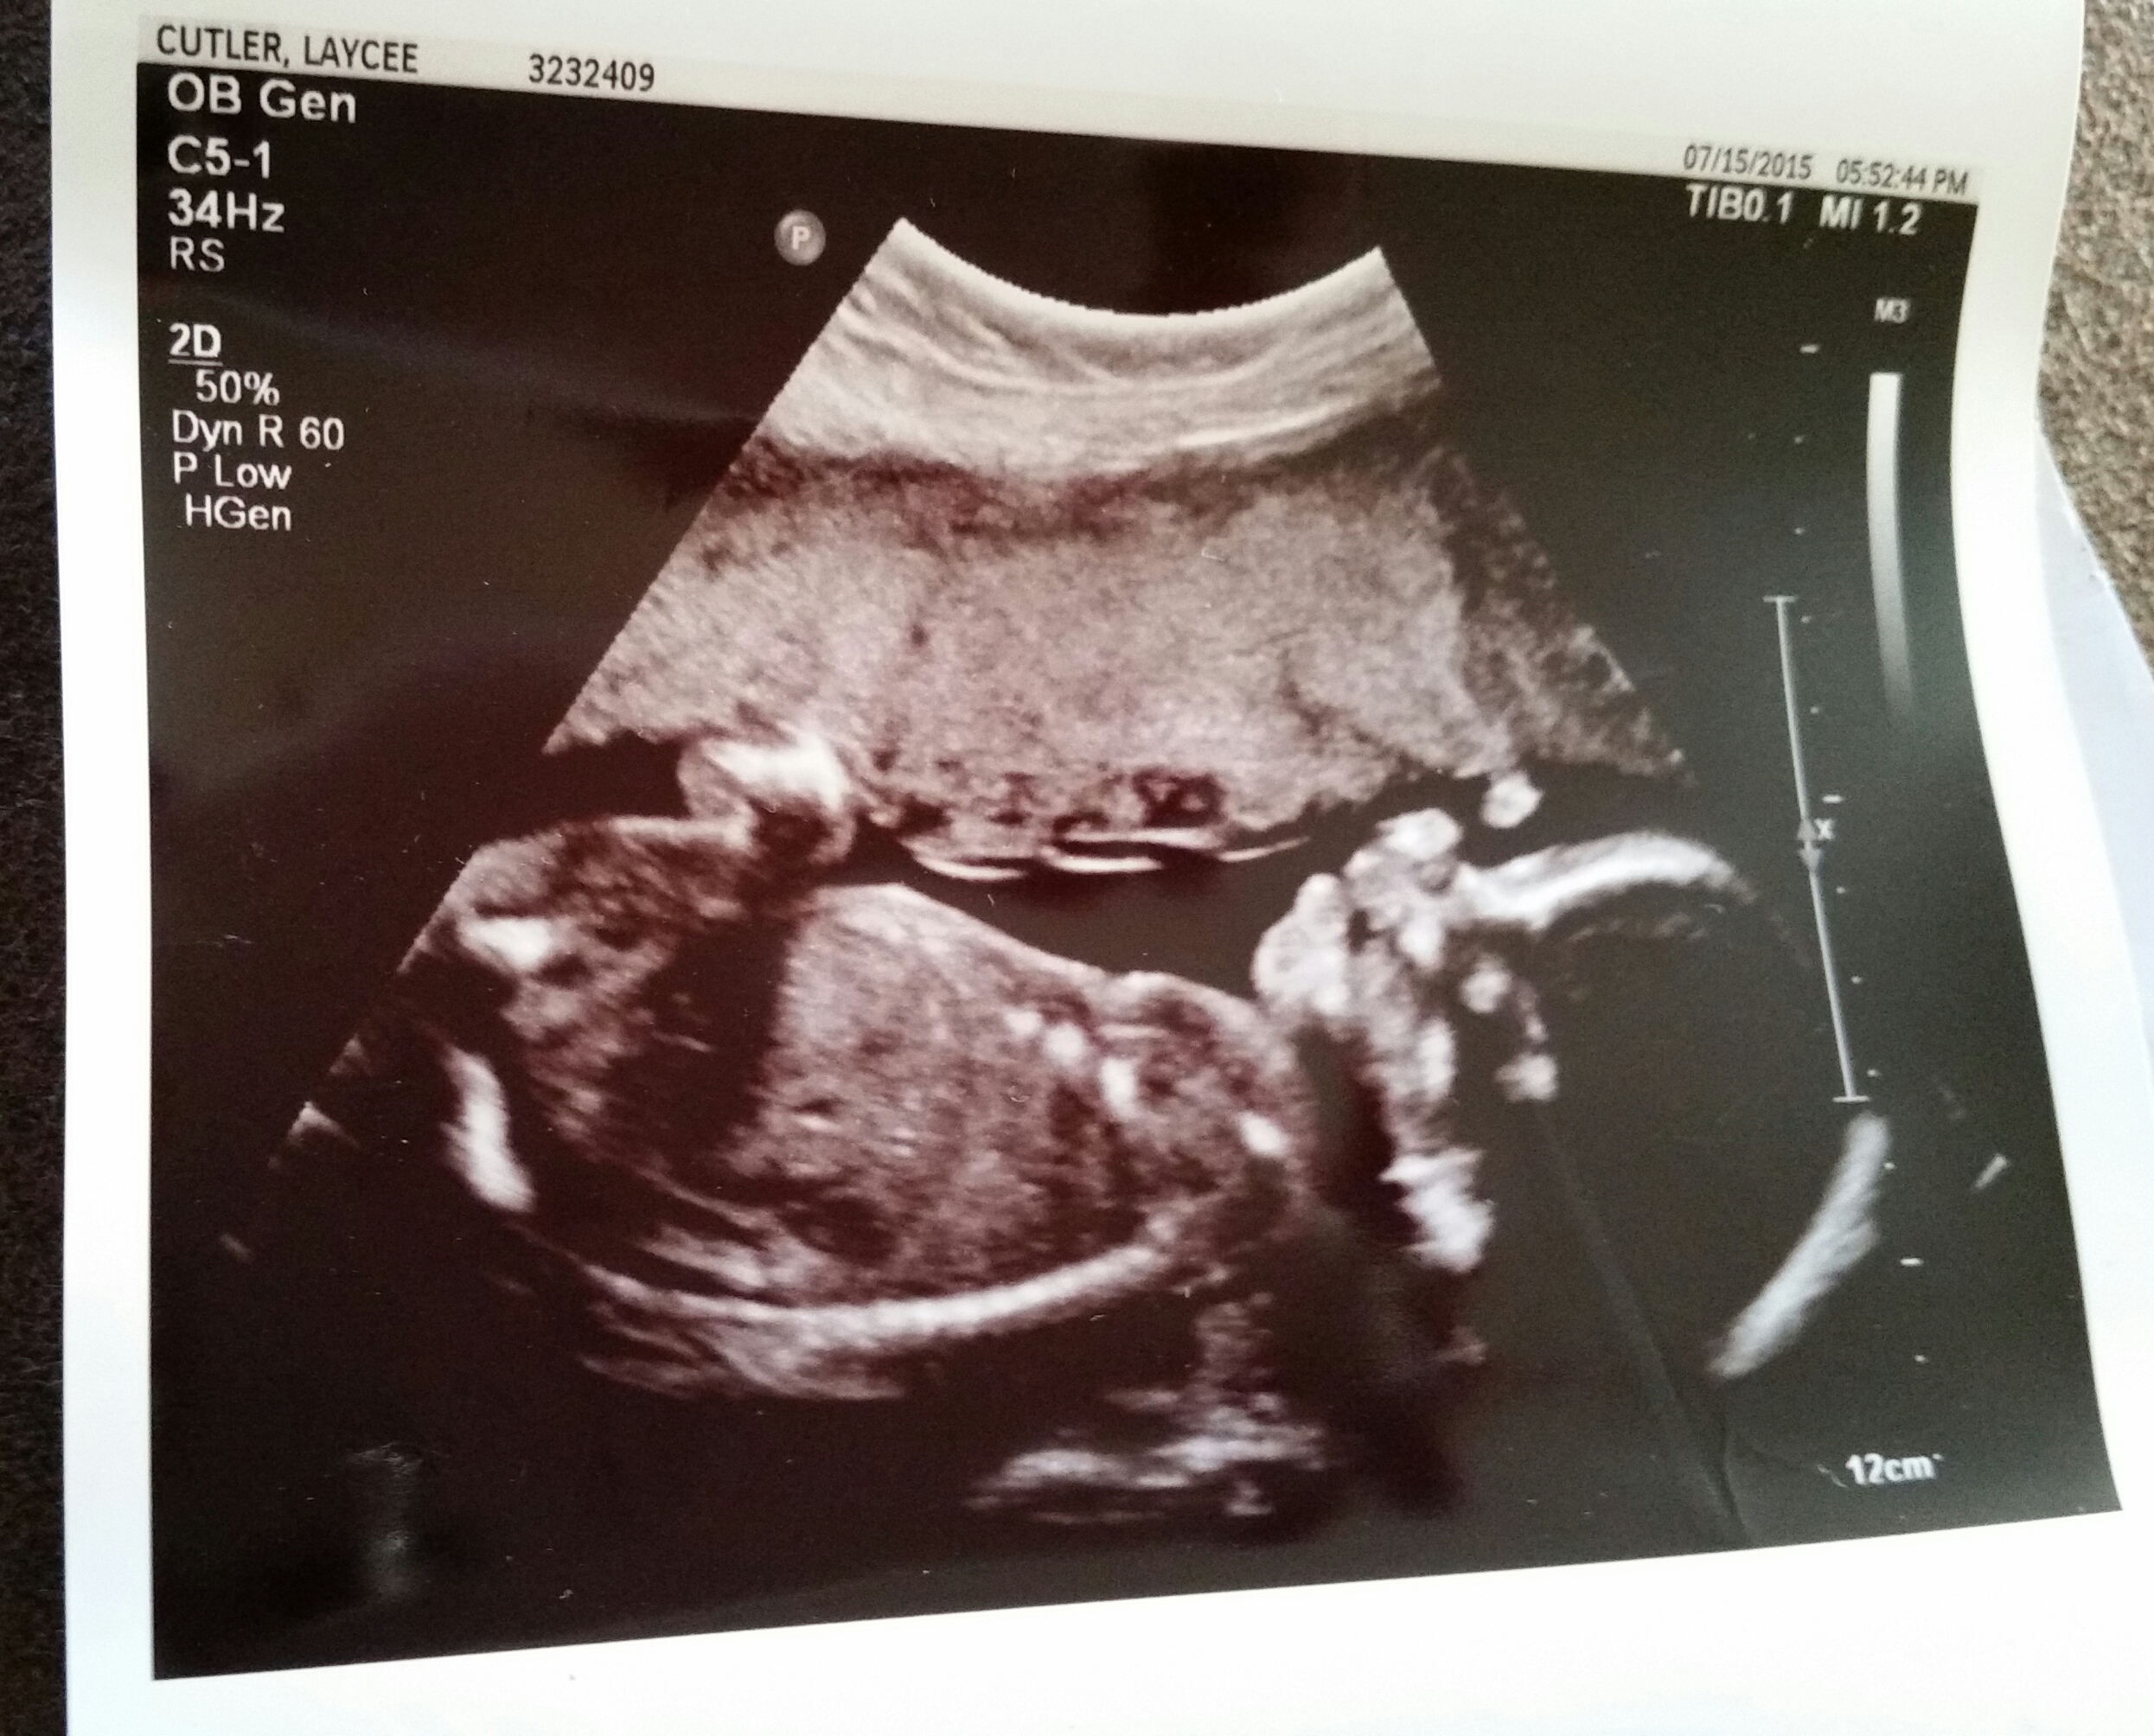

Hey all you mama's of girls I'm a mama of boys and I'm really hoping maybe you all would know if there is any hope of this ultrasound picture being swollen girlie parts and not tiny boy parts. I feel that this baby is a girl but tech said 100% boy, I don't see it. She gave me the best shot she could get and it looks nothing like my other two boys. Please give me some good honest advice even if it's not what I really want to hear I need to hear it. Attachment 26385Attachment 26386Attachment 26387